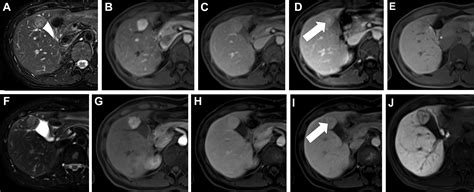

The primary purpose of adding a contrast agent during your scan is to improve the visibility of internal structures. Without contrast, some tissues may appear similar in density, making it difficult for a physician to identify subtle abnormalities. By using a contrast agent, the substance travels through your blood vessels and accumulates in areas of increased blood flow, such as tumors, areas of inflammation, or damaged blood vessels. This “enhancement” makes these areas appear brighter or more defined on the resulting images.

• Detecting tumors: Contrast helps distinguish between benign and malignant growths by showing how much blood supply they receive.

After the scan is complete, the images are sent to a radiologist. They analyze the scan to compare the non-contrast and contrast-enhanced images. The “enhancement” patterns allow the radiologist to write a detailed report for your primary physician. This report usually outlines findings in clinical terms, noting the presence or absence of abnormalities. It is important to remember that the MRI report is just one part of your diagnostic puzzle; your doctor will correlate these results with your physical exam and other lab findings to finalize a diagnosis and treatment plan.